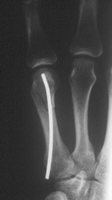

Stabilisierung der MHK Schaftfraktur. Übungsstabilität und freie Funktion der Hand sind postoperativ möglich.

Schaftfraktur des 5. Mittelhandknochen durch schlag. Der Patient hat eine Nickelallergie. Hier wird die Fraktur in i.V. - Anästesie reponiert und mit einem 2mm Titandraht stabilisiert. Diese Versorgung ist stabil genug für eine frühfunktionelle Behandlung. Vorteil ist auch hier, dass es nicht zur Bewegungsbehinderung im Grundgelenk kommt.